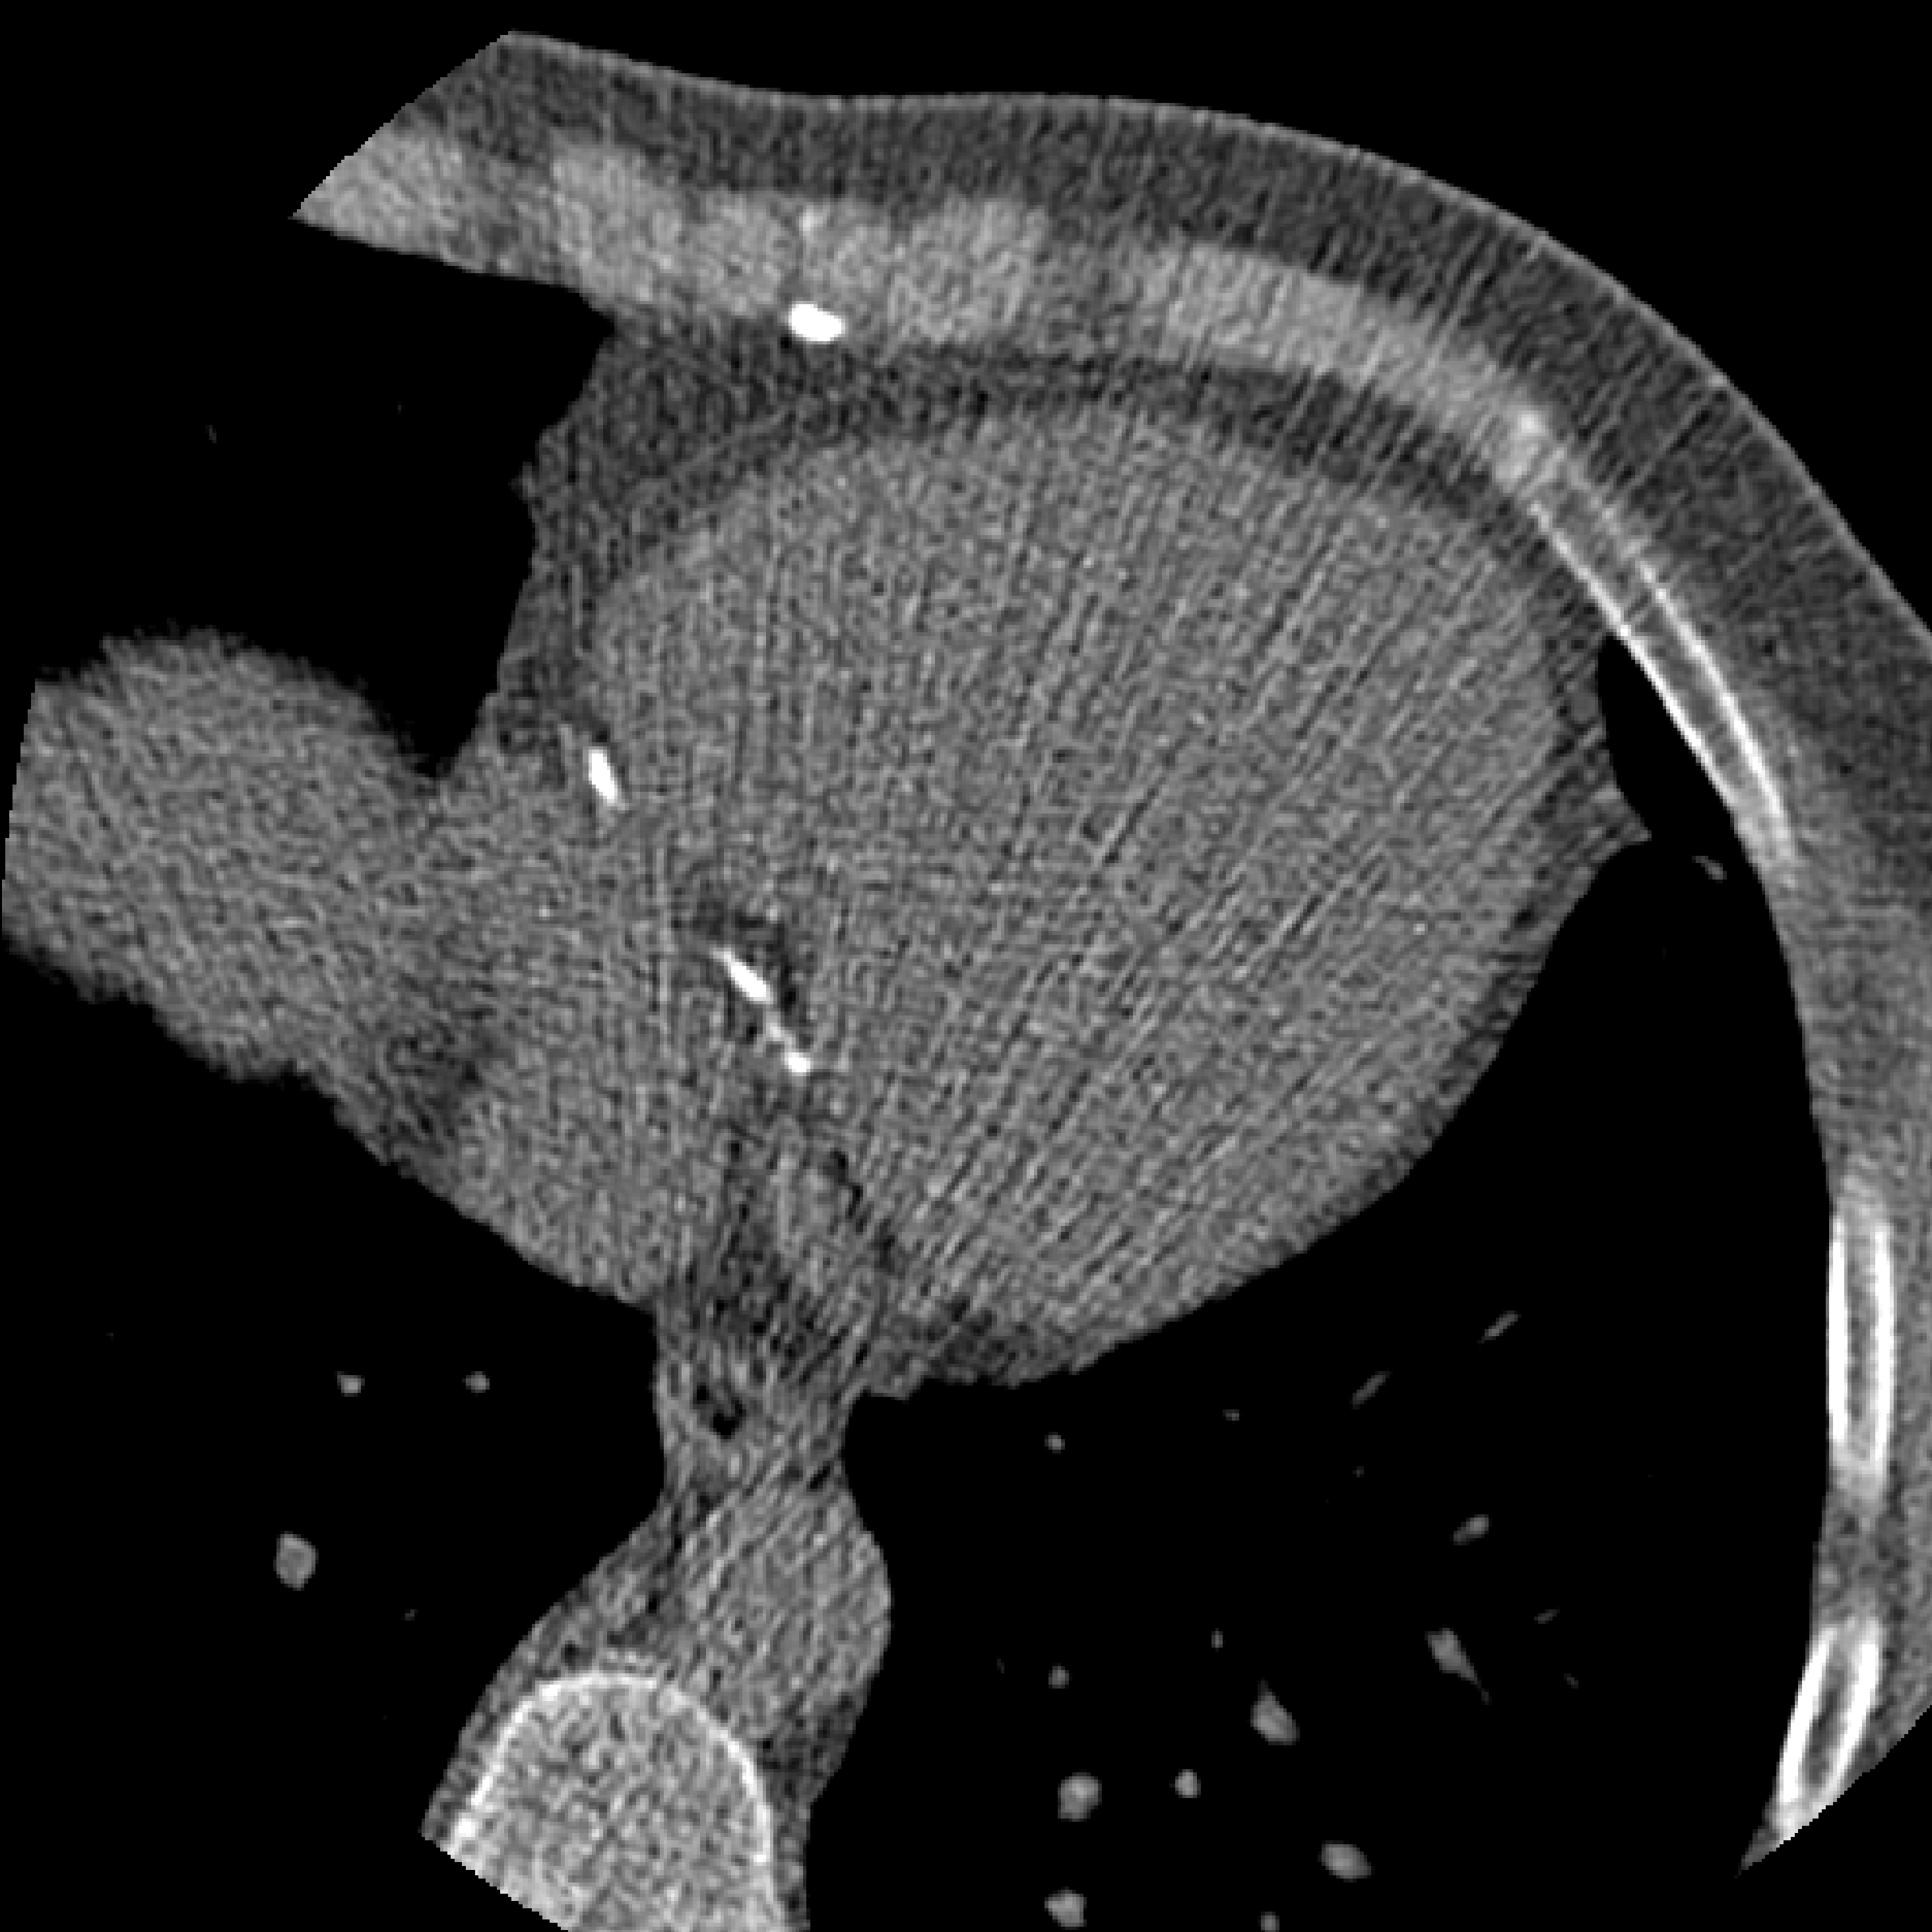

Figure 9: Result from Wolterink et al. [40]. Example CT slice of LABEL:sub@subfig:vivo20fbp 20% low-dose FBP reconstruction and LABEL:sub@subfig:vivo20fbpcac corresponding coronary artery calcification (CAC) scoring mask, LABEL:sub@subfig:vivo20g3 20% dose GAN-based noise reduction and LABEL:sub@subfig:vivo20ircac corresponding CAC scoring mask, 20% dose iterative reconstruction (IR) and LABEL:sub@subfig:vivo20ircac corresponding CAC scoring mask, and LABEL:sub@subfig:vivo100fbp routine-dose FBP reconstruction and LABEL:sub@subfig:vivo100fbpcac corresponding CAC scoring mask. All images have window level/width 90/750 HU. CAC scoring masks show all voxels 130absent130\geq 130 HU in black, and voxels selected by CAC scoring with connected component labeling in red.

Medical image acquisition often includes a trade-off between image quality and factors such as time, costs and patient discomfort. For example, lower ionizing radiation dose levels in CT could prevent radiation-induced cancer, but will typically lead to increased image noise levels, and undersampled MR image reconstruction could reduce scan time but may lead to image artifacts. Adversarial methods have been used to avert such effects in the acquisition domain or the image domain.

To allow CT scanning at low radiation dose, regression CNNs have been proposed to convert low-dose CT images to routine-dose CT images [41]. One problem is that even routine-dose CTs contain low amounts of image noise, and training a regression model can lead to blurred predictions. Wolterink et al. [40] proposed a 3D model to translate low-dose CT images into routine-dose CT images. The method was evaluated on phantom CT data as well as in-vivo CT images. In phantom CT images, where the low-dose CT and routine-dose CT image were perfectly aligned, the adversarial loss was combined with an L1𝐿1L1-loss term between the generated image and a reference routine-dose CT image. In real cardiac CT studies, low-dose and routine-dose images were not aligned and self-regularization was used (Eq. 8). Fig. 9 shows a low-dose CT image and the same image denoised using the proposed method or by commercially available iterative reconstruction (IR) software. Both denoising methods compare well with the reference routine-dose CT. However, IR requires CT projection data to be available, while the adversarial method operates on already reconstructed CT images.